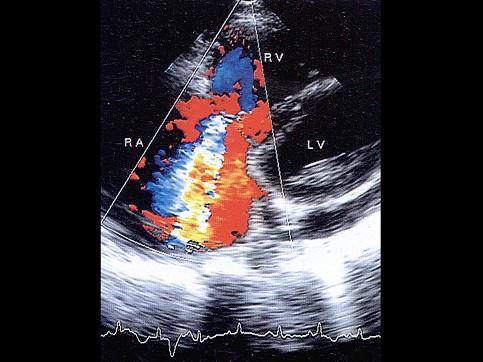

问题 该图基线下方频谱速度为4.2米/秒,提示肺动脉高压程度为?(?)

选项 A.轻度 B.中度 C.重度 D.轻微 E.无

答案 C